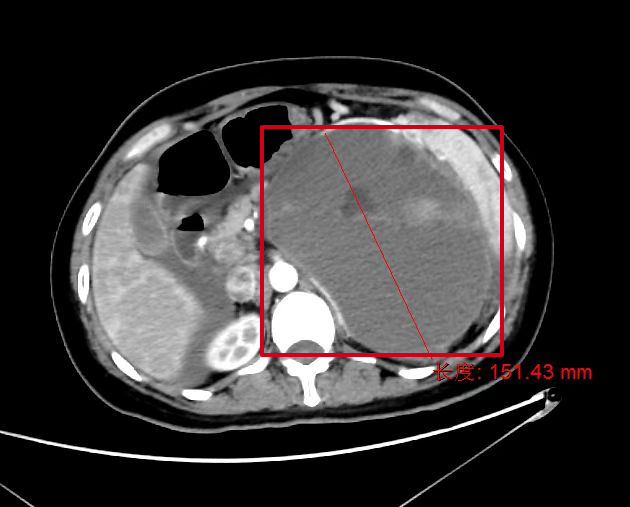

患者爲40歲左右的中年女性,因腹痛在惠州市第六人民醫院急診醫學(xué)科行腹部CT檢查後(hòu)提示胰腺腫瘤收入胃腸肝膽外科,其實患者于15年前就(jiù)已發(fā)現胰腺腫瘤的存在,當時(shí)腫瘤體積小、考慮良性可能(néng),且尚未造成(chéng)不适症狀,故一直未予以積極治療。患者入院後(hòu)完善增強CT檢查,提示胰體尾腫瘤不排除惡性腫瘤、胰源性門脈高壓、脾髒增大。

标注所示爲巨大腫瘤